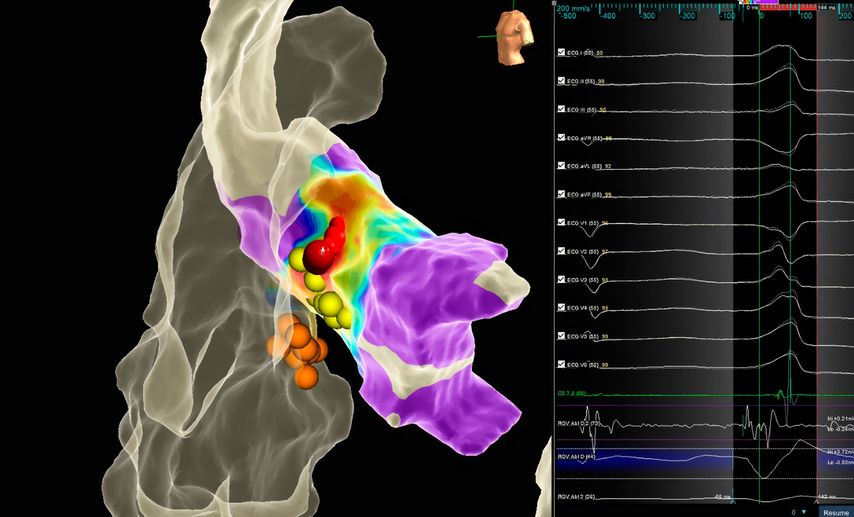

Die Katheterablation von symptomatischen ventrikulären Extrasystolen (VES) oder monomorphen ventrikulären Tachykardien (VT) ohne zugrunde liegende strukturelle Herzerkrankung stellt laut aktuellen ESC-Leitlinien6 im Falle von aus dem rechtsventrikulären Ausflusstrakt (RVOT) kommenden Arrhythmien oder faszikulären Tachykardien eine Klasse-I-Indikation dar. Bei anderen idiopathischen VES/VT-Lokalisationen, z.B. aus dem linksventrikulären Ausflusstrakt (LVOT) entspringenden ventrikulären Arrhyth-mien, ist zunächst ein medikamentöser Therapieversuch mittels Betablockern oder Kalziumkanalblockern indiziert (Klasse-I-Empfehlung), bevor eine Katheterablation in Erwägung gezogen wird (Klasse-IIa-Empfehlung). Dies ist durch die doch komplexere Ablationsprozedur bedingt, da insbesondere LVOT-Arrhythmien oftmals einer Katheterablation schwerer zugänglich sind (Fokus im Aortensinus, im distalen Koronarsinus/„great cardiac vein“). Gegebenenfalls kann ein Ablationsverfahren von mehreren Herzhöhlen ausgehend notwendig sein, entweder konsekutiv (Abb. 2) oder mittels bipolarer Ablation, wo mithilfe eines speziellen Generators die gleichzeitige Energieabgabe über zwei Katheter simultan erfolgen kann.7

Abb. 2: Links: 3D-Rekonstruktion und Aktivierungsmapping mittels multipolaren Mapping-Katheters und erfolgreiche Ablation einer ventrikulären Extrasystolie vom „left ventricular summit“ mittels konsekutiver Energieabgabe im rechtsventrikulären Ausflusstrakt (links im Bild) und linksventrikulären Ausflusstrakt/Aortensinus (mittig – rote Punkte) sowie im distalen Koronarsinus am Übergang zur „great cardiac vein“ (gelber Punkt). Rechts: Kontrastmitteldarstellung des linkskoronaren Aortensinus mittels Kontrastmittelgabe über den Ablationskatheter vor Ablation (unmittelbare Nähe zum Abgang des linken Hauptstamms und zum biologischen Aortenklappenersatz)

Die hochauflösenden 3D-Mapping-Systeme sind insbesondere dann von kritischer Bedeutung, wenn sehr sensible Strukturen im Rahmen der Ablation geschont werden sollen. In Abbildung 3 ist die erfolgreiche Ablation einer Ausflusstraktextrasystolie im Bereich der Aortenwurzel in unmittelbarer Nähe zum intrinsischen Reizleitungssystem (HIS-Signale) dargestellt.

Abb. 3: Elektroanatomische Rekonstruktion mit Aktivierungsmapping des linksventrikulären Ausflusstrakts/Aortenwurzel mit Ursprung der Extrasystolie in unmittelbarer Nähe zum intrinsischen Reizleitungssystem (HIS-Signal, gelbe Punkte). Erfolgreiche Ablation (rote Punkte) mit vorsichtiger Annäherung an die HIS-Punkte ohne Verlängerung der PQ-Zeit